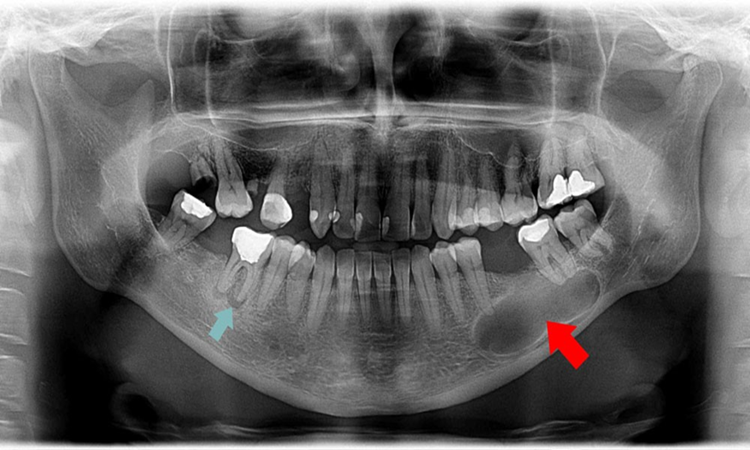

عصب کشی دندان های آسیاب

چرا دندان های آسیاب بیشترین آمار عصب کشی را دارند؟

دندان های آسیاب به دلیل موقعیت و ساختار خاصشان بیشترین فشار جویدن را تحمل می کنند و سطح آن ها پر از شیار و حفره های ریز است که غذا و باکتری ها را در خود جمع می کند. همین عوامل باعث می شود پوسیدگی در این دندان ها سریع تر ایجاد شود و به پالپ (عصب دندان) برسد، در نتیجه نیاز به درمان ریشه (عصب کشی) افزایش پیدا می کند.